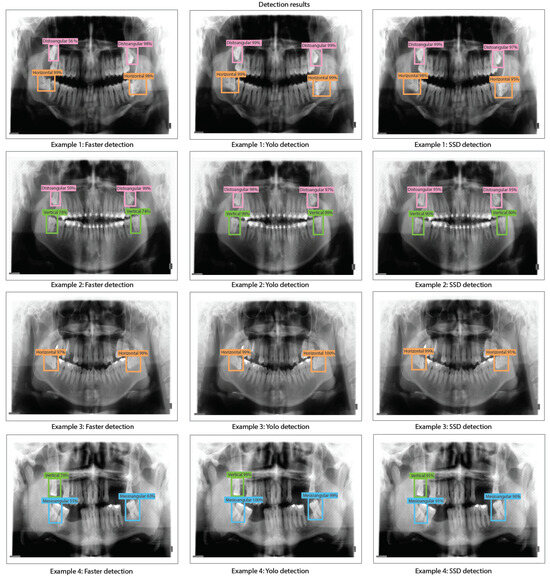

- We train, validate, and test DL-based object detection algorithms based on the You Only Look Once V2 (or YOLO V2), Faster Region-Convolutional Neural Network (Faster R-CNN), and Single Shot Multi-box detector (SSD). We compare the performance of each object detection model by using ResNet-18, ResNet-50, and ResNet-101 for the feature extraction stage of each detector.

- We present our results by using precision-recall curves in the proposed dataset. In addition, we evaluated bias, variance, overfitting, and underfitting for each model trained based on YOLO V2, Faster R-CNN, and SSD for the proposed dataset along with detection results and comparison tables of detection percentages.

- We obtained the best results for Faster R-CNN using ResNet-18 were reached in test 2 (training: 25%, validation: 24%, and testing: 39%). For YOLO V2 using ResNet-18, the best result is test 10 (training: 99%, validation: 90%, and testing: 96%). Finally, for the SSD model using ResNet-18, the best result was in test 12 (training: 87%, validation: 82%, and testing: 81%). This indicates that the best model for this experiment set is YOLO V2 using ResNet-18 with the hyper-parameter configuration of test 10. This model has a low bias and variance, demonstrating high generalizing capabilities (no overfitting) since the accuracy is barely reduced from training to validation and testing. We can observe the training, validation, and testing results for models obtained in tests 2, 10, and 12 in Figure 10, in which we present the precision-recall curves for such models.

- We obtained the best results for YOLO V2 using ResNet-50 in test 18 (training: 99%, validation: 89%, and testing: 95%). For the SSD model using ResNet-50, the best result was in test 9 (training: 88%, validation: 91%, and testing: 88%). This indicates that the best model for this set of experiments is YOLO V2 using ResNet-50 with the hyper-parameter configuration of test 18. This model has a low bias and variance, demonstrating high generalizing capabilities (no overfitting) since the accuracy is barely reduced from training to validation and testing. We can observe the training, validation, and testing results for models obtained in tests 11, 18, and 9 in Figure 12 in which we present the precision-recall curves for both models.

- We obtained the best results for YOLO V2 using ResNet-101 in test 11 (training: 99%, validation: 92%, and testing: 99%). For the SSD model using ResNet-101, the best result was in test 12 (training: 88%, validation: 90%, and testing: 89%). This indicates that the best model for this set of experiments is YOLO V2 using ResNet-101 with the hyper-parameter configuration of test 11. This model has a low bias and variance, demonstrating high generalizing capabilities (no overfitting) since the accuracy is barely reduced from training to validation and testing. We can observe the training, validation, and testing results for models obtained in tests 5, 11, and 12 in Figure 14 in which we present the precision-recall curves for both models.

- During the implementation of third-molar detection algorithms using different detection models and ResNet architectures, it can be observed that YOLO V2 is the model that stands out in terms of both accuracy and consistency during the training, validation, and testing stages. Therefore, the best results from our experiments were obtained by YOLO V2 using ResNet-18 (training: 99%, validation: 90%, and testing: 96%), YOLO V2 using ResNet-101 (training: 99%, validation: 92%, and testing: 99%), and YOLO V2 using ResNet-101 (training: 99%, validation: 92%, and testing: 99%), which indeed are very similar. These high accuracy results indicate that YOLO V2 is very effective for detecting third molar angles in our X-ray dataset distribution. On the other hand, the Faster R-CNN models with ResNet CNNs (ResNet-18, ResNet-50, and ResNet-101) possess underfitting problems for our X-ray dataset distribution. This might be because the Faster R-CNN is characterized by using an RPN (Region Proposal Network) stage. On the other hand, the SSD detection model has moderate accuracy across all ResNet architectures. Although SSD does not achieve the accuracy levels of YOLO V2, it produces reasonably consistent results, making it suitable for applications that require a balance of accuracy and detection speed (inference times less than 100 ms).

- Overall, we have demonstrated in this work that CNN-based object detection techniques can be used to detect third-molar angle detection based on Winter’s classification criterion. The categories that we detected are distoangular, vertical, mesioangular, and horizontal. To detect these categories, we have implemented several object detection methods, which are YOLO V2, Faster R-CNN, and SSD. Each of the mentioned object detection methods was trained by using ResNet-18, ResNet-50, and ResNet-101 as feature extraction methods, in which YOLO V2 with ResNet-18 obtained the best results (training: 99%, validation: 90%, and testing: 96%). These findings represent a promising solution for dentistry applications, such as improved diagnostic accuracy, more automated dental procedures, and even a possible training tool for educational applications. Moreover, we have presented a significant improvement compared to other works, that only train a single object detection method for different applications such as third molar detection and angle detection, tooth identification, caries detection, dental implant detection, and crown detection (see Table 7).

- Based on the times of inference presented, YOLO V2 demonstrates a strong potential for real-time clinical applications, with inference times that vary from 0.071 to 0.092 s in different Resnet architectures. This positions it well inside the desirable threshold of fewer than 0.3 s (real-time) for quick decision-making in clinical environments. SSD is also promising, with inference times between 0.077 and 0.104 s, so it is a viable option for scenarios that require rapid responses. In contrast, Faster R-CNN is not faster, with inference times from 0.188 to 0.360 s, it is less suitable for real-time use due to its slower processing speed, and in our case, it also presents a poor performance in detection. In general, Yolo V2 stands out as the most effective model for the detection of third molar angles in real-time in clinical environments.